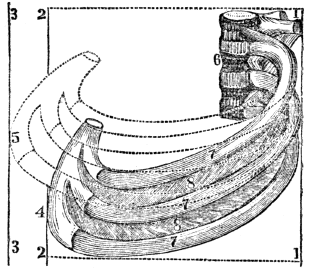

| 23. | Anatomy of the Respiratory Organs, | 209 |

| 24. | Physiology of the Respiratory Organs, | 217 |

| 25. | Hygiene of the Respiratory Organs, | 228 |

| 26. | Hygiene of the Respiratory Organs, continued, | 239 |

| 27. | Animal Heat, | 252 |